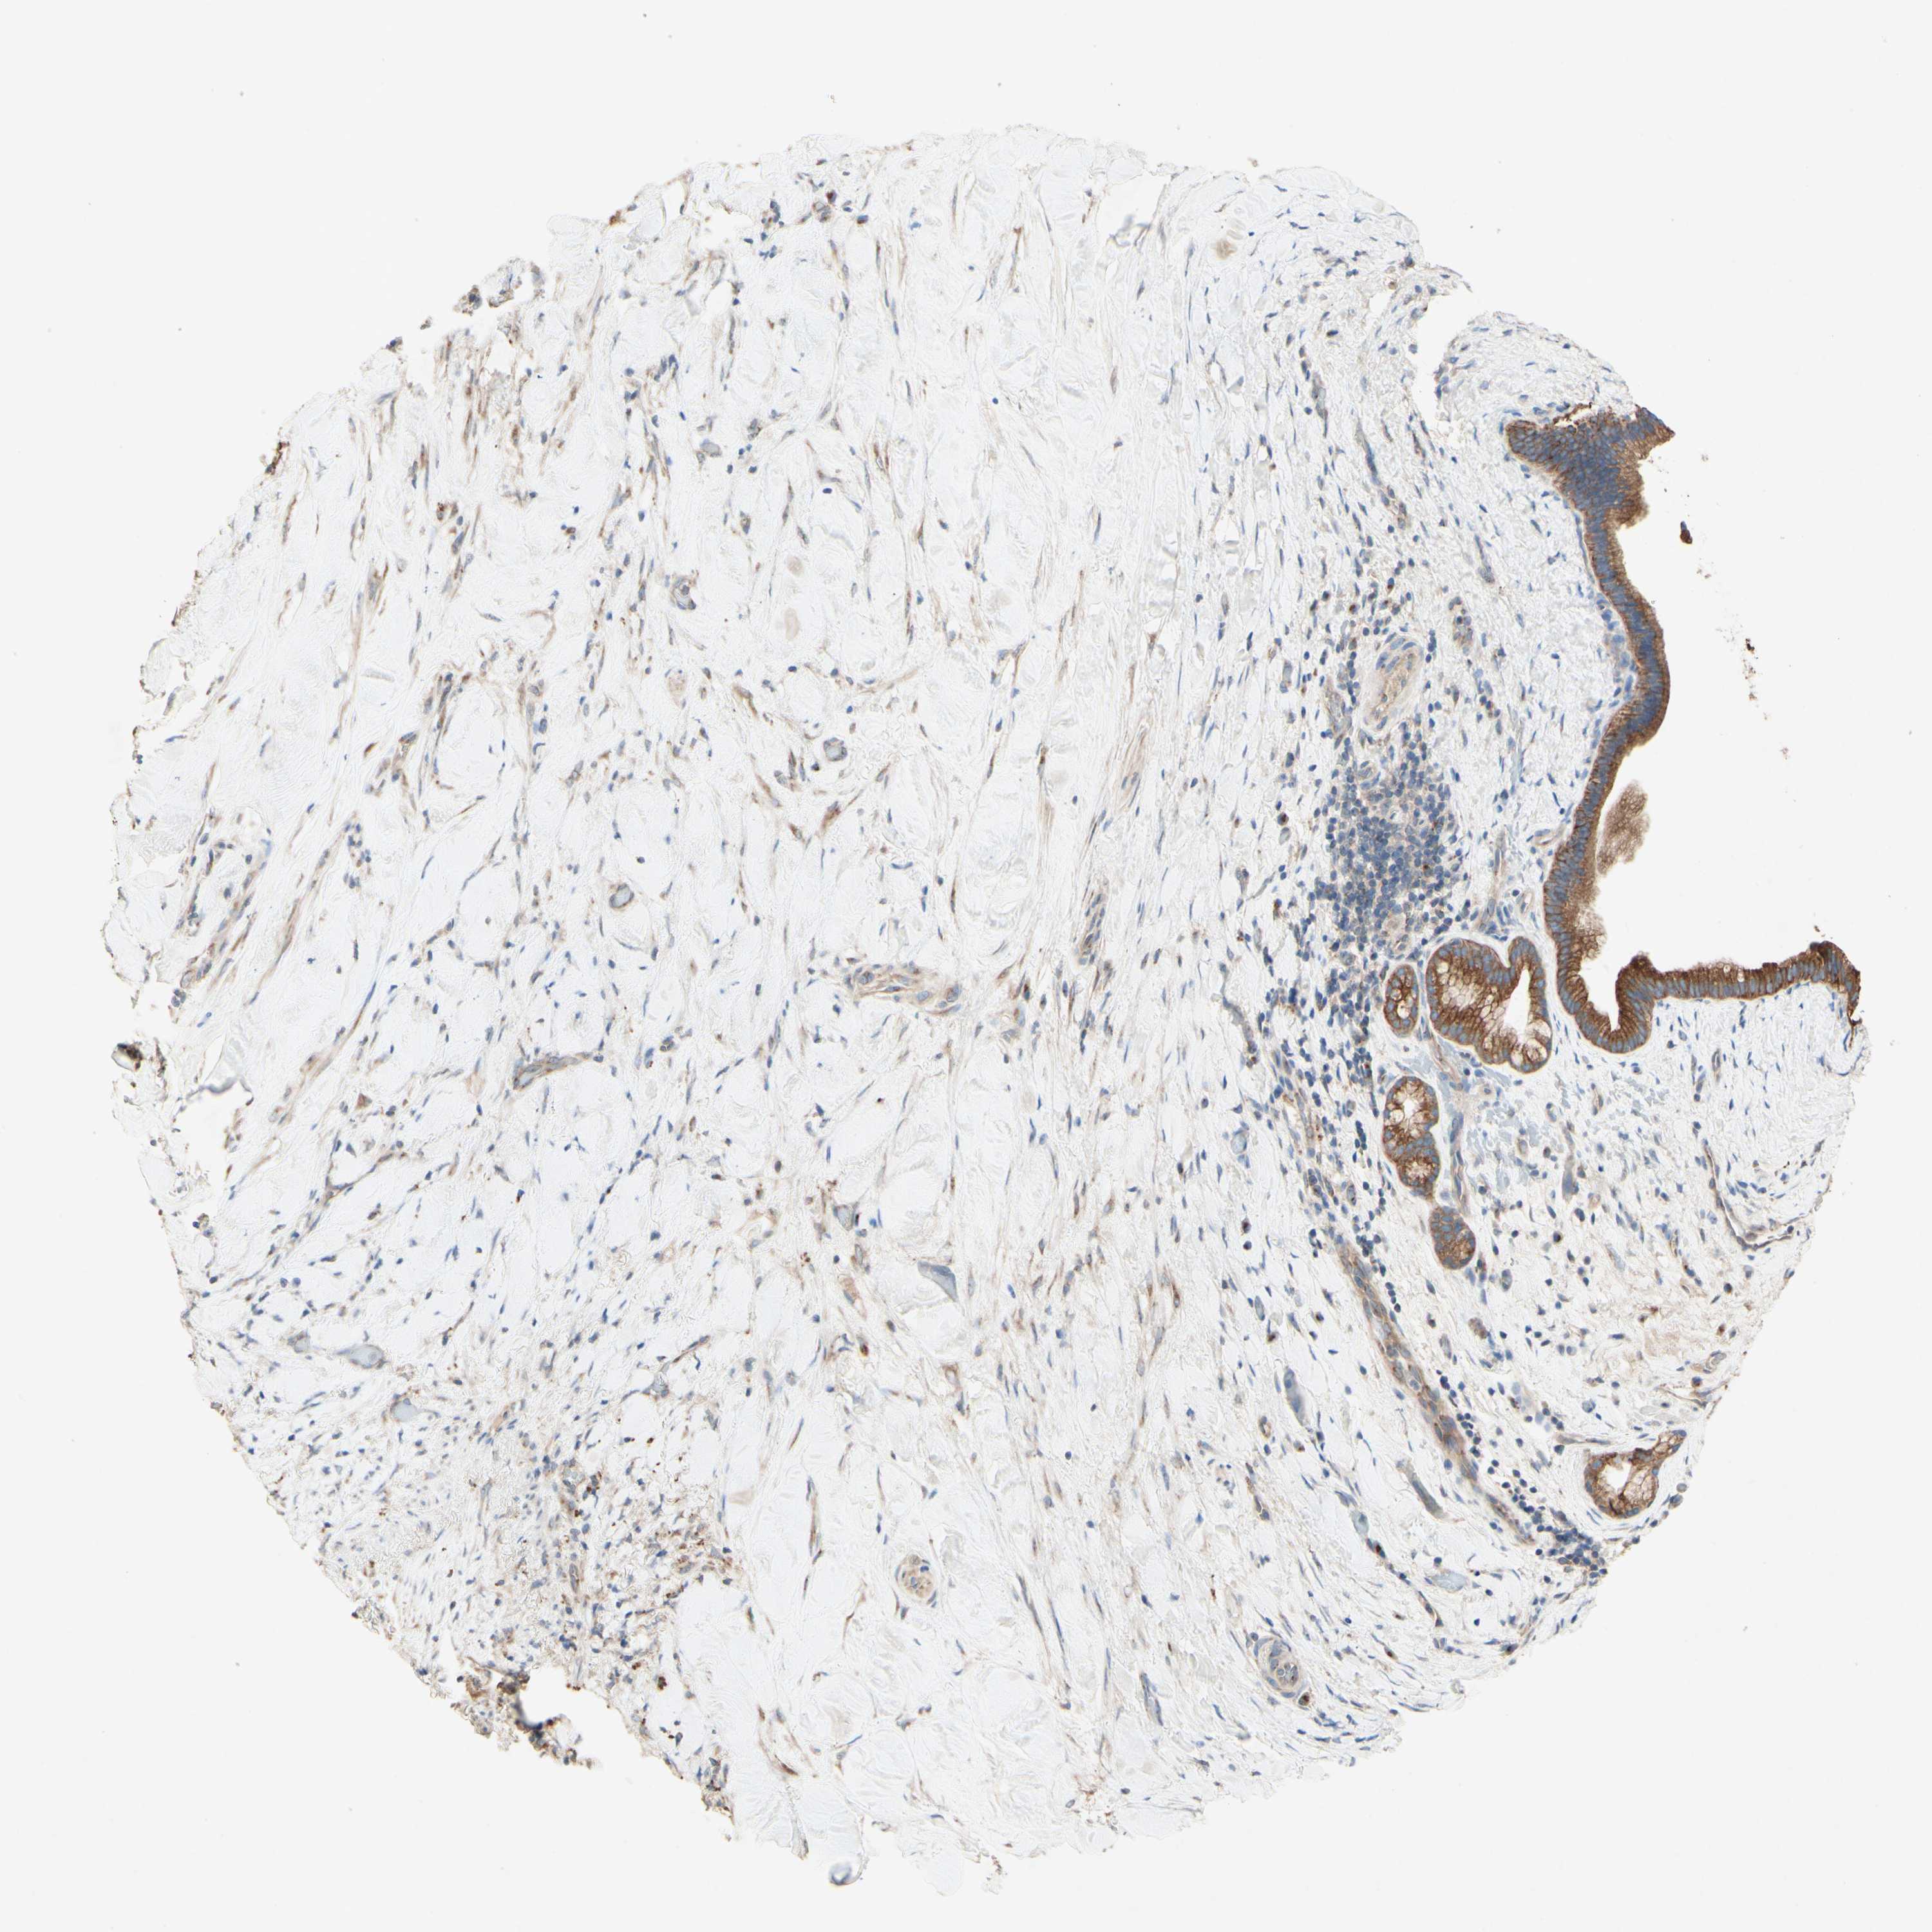

LIVER CANCER - Protein expressioni

A mouse-over function shows sample information and annotation data. Click on an image to view it in a full screen mode. Samples can be filtered based on level of antibody staining by selecting one or several of the following categories: high, medium, low and not detected. The assay and annotation is described here.

Antibody stainingi

Antibody staining in the annotated cell types in the current human tissue is reported as not detected, low, medium, or high, based on conventional immunohistochemistry profiling in selected tissues. This score is based on the combination of the staining intensity and fraction of stained cells.

Each image is clickable and will lead to virtual microscopy that enables deeper exploration of all samples and also displays staining intensity scores, fraction scores and subcellular localization as well as patient and tissue information for each sample.

Antibody HPA010008

Antibody HPA010665

Staining

High

Medium

Low

Not detected

Intensity

Strong

Moderate

Weak

Negative

Quantity

>75%

75%-25%

<25%

None

Location

Nuclear

Cytoplasmic/membranous

Cytoplasmic/membranous,nuclear

Cholangiocarcinoma

Carcinoma, Hepatocellular, NOS